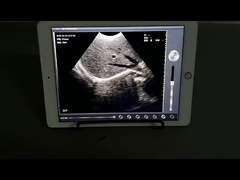

Calidad Escáner de ultrasonido portátil, analizador del ultrasonido del PDA Fabricante de China

Ultrasound scanner